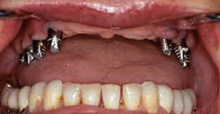

Notre longue expérience dans la régénération de l’os publiée dans des article et conferances dentaires nous a permis de redonner à nos patients des dents fixes à la place des dentiers. Elle s’applique surtout à la régénération de la mâchoire supérieure et des sinus maxillaires.

Extrait de la conférence du docteur Farsirotu sur le sujet de la régénération osseuse et des sinus maxillaires avec des facteurs de croissance de l’os pour obtenir une dentition fixe sur implants.

Sujet : Les dernières découvertes dans la régénération osseuse et les implants dentaires